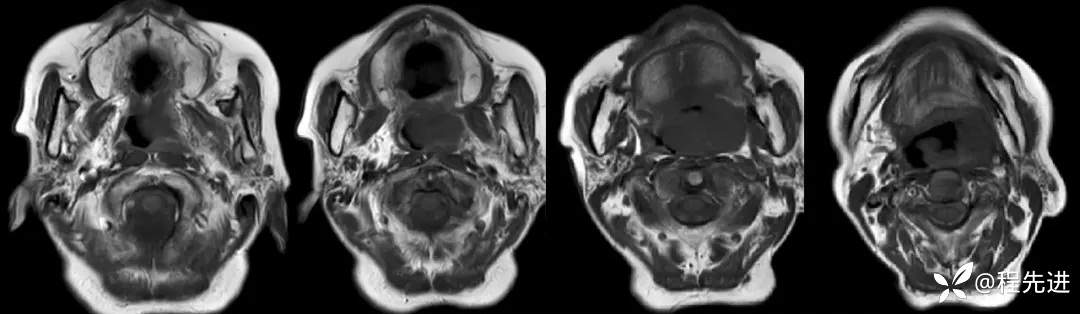

MRI平扫+增强:

T1: